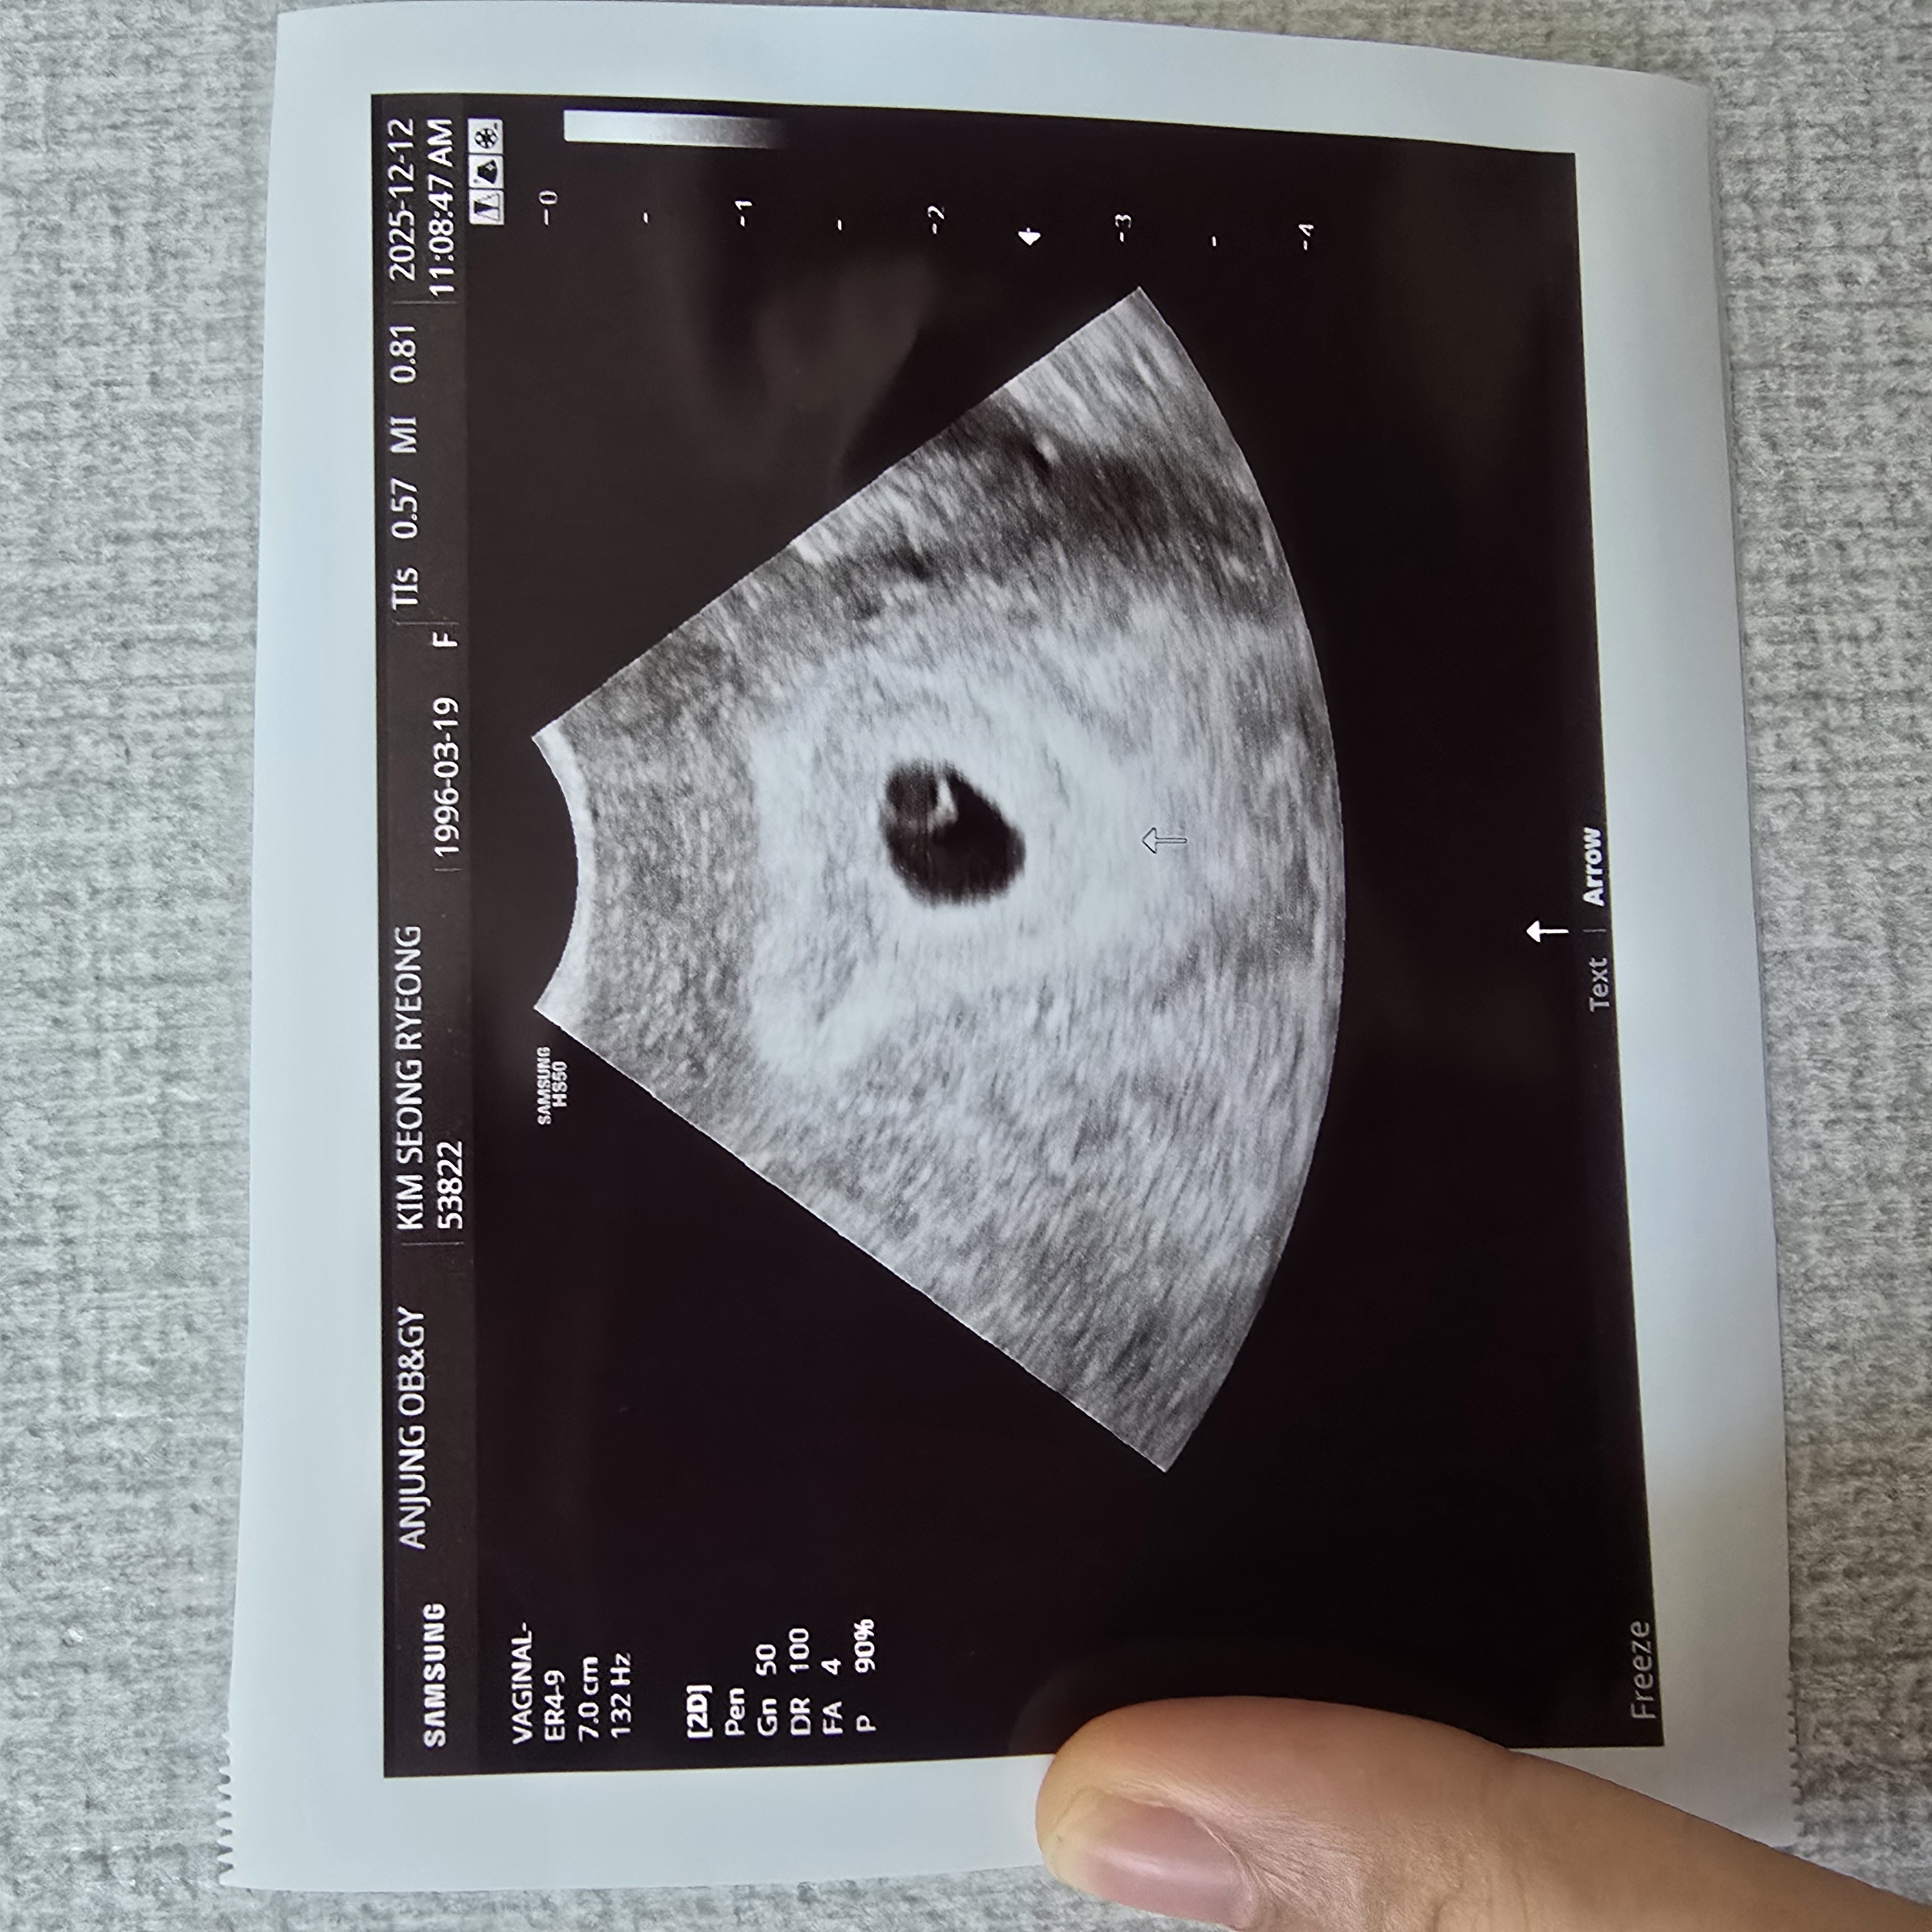

오늘 아기집 보고 왔는데

오늘4주6일째 되는날 아기집 보고 왔는데 잘크고 있다 하시고 독감주사(무료)랑 보건소에서 산전검사 했던거 빼고 검사했는데 병원비가7만 8천원 나왔는데 보통 이정도 나오는게 맞나요?? 아기집은 잘 나온게 맞을까요? 설명을 잘 안해주셔서 병원이 여기 한곳이라 갈때마다 사람이 많고 대충해주는것 같은 느낌이 드네요 ㅠㅠ